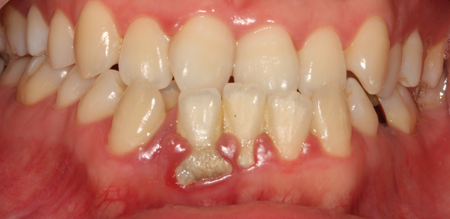

치주치료 전후사진

치주염 (중기~말기)

주기적으로 잇몸이 붓고 피가 나며, 욱씬하거나 우리한 통증이 나타남.

치주치료 및 정도에 따라 치주수술(잇몸수술)이 필요함. 향후 관리 정도에 따라 3~6개월 간격으로 내원하여 유지치료를 시행하여야 함.